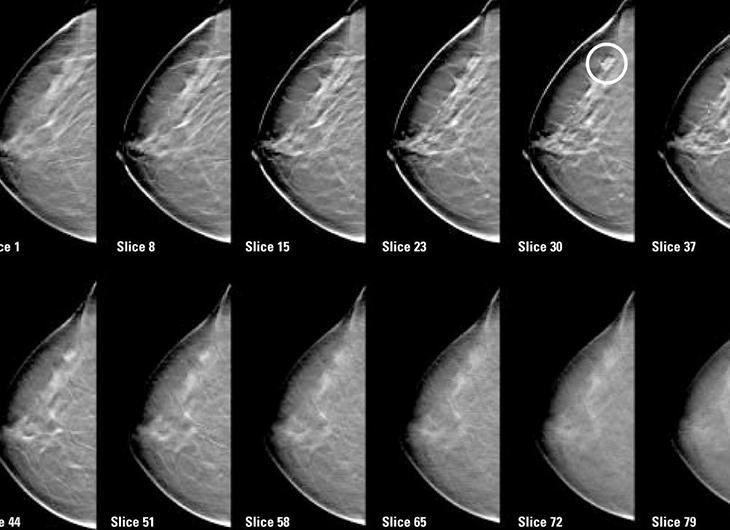

Цифровая маммография — очень результативный и надежный способ диагностики заболеваний молочных желез, на снимках хорошо визуализируются опухоли размером до 5-6 мм и патологически измененные лимфатические узлы, что позволяет своевременно поставить правильный диагноз и начать лечение. Очень многим женщинам этот метод диагностики сохранил здоровье и даже жизнь.

Цифровая маммография — более современный метод, цифровые маммограммы отличает более высокая точность.

Данный вид является скрининговым методом и подходит для обследования большого количества женщин на предмет раннего выявления опухолевой патологии молочных желез. Снимки выполняются в 2-х и более проекциях.

Для проведения необходим специальный аппарат — маммограф, используются рентгеновские лучи. Данные поступают на компьютер, анализ проходит автоматически. Изображения можно рассматривать с любого ракурса с помощью специальной программы.